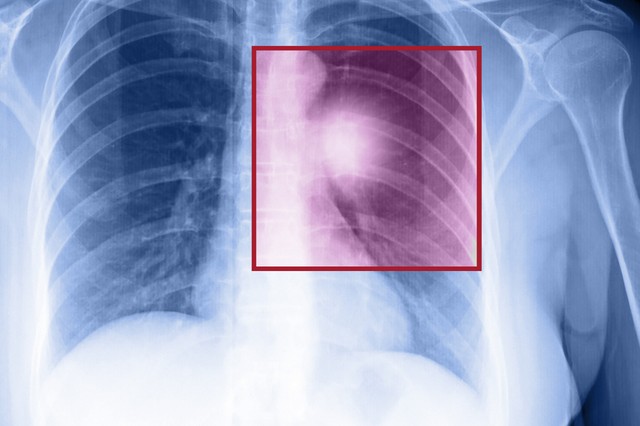

Ezekkel a vizsgálatokkal már a tünetek előtt kiszűrhető a tumor

Összegyűjtöttük, milyen vizsgálatokkal mutatható ki még a tünetek megjelenése előtt a tumor.